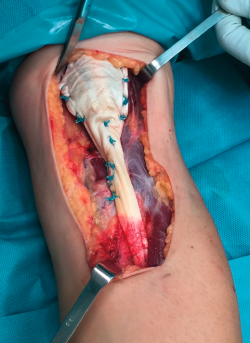

La técnica de sutura del injerto de Aquiles fue la de tipo FiberLoop distalmente y anclamos el tendón mediante un botón cortical (EndoButton®, Smith & Nephew) en disposición intramedular en la tuberosidad bicipital del radio para evitar el riesgo de lesión del nervio radial. La sutura proximal fue mediante puntos de tipo Krakow intentando envolver el muñón muscular en toda su circunferencia utilizando la parte proximal del tendón de Aquiles como un abanico desplegado (Figuras 2 y 3).

Figura 3. Imagen de la sutura proximal del injerto.